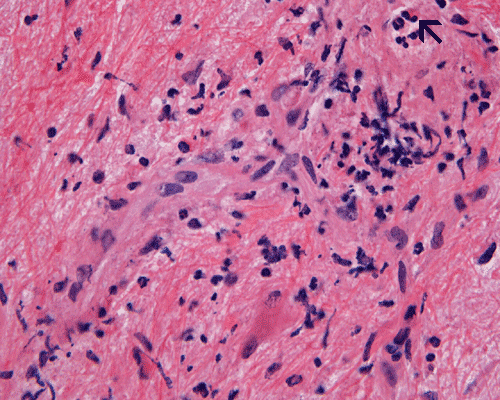

Panel A to E are MR images. Panel F and G are taken from intraoperative cytologic preparation. Panel H to M are taken from frozen section. Panel N and O are from paraffin section. These sections are stained by hematoxylin-eosin stain. Panel P is immunohistochemistry for neurofilament proteins. Panel Q is stained by Luxol fast blue-Periodic acid Schiff (LFB-PAS) stain.

| DIAGNOSIS: Eosinophilic myelitis. |

Pathology of eosinophilic myelitis

Eosinophilic myelitis is featured by lymphocytic infiltration accompanied by a varying intensity of eosinophils. Both the myelin and axons may be damaged. Axonal spheroids can be seen and indicate primary axonal damage rather than secondary damage following demyelination 14, 15. Destruction of axons in the lesion may well explain the relatively poor recovery of this condition. There is increase in eosinophils in CSF in the our under discussion. However, the CSF studies are normal in two previous studies 14, 15.

The eosinophils play an important role in causing the damages. Infiltration by eosinophils and depositions of activated products of eosinophils are commonly seen in atopic disorders, such as atopic bronchial asthma, allergic rhinitis and atopic dermatitis. The presence of atopic diathesis as well as eosinophilic cationic protein deposition suggests that atopy may represent one of the risk factors for developing eosinophilic myelitis. Eosinophilic cationic protein is one of the neurotoxic proteins released by activated eosinophils Eosinophil cationic protein and other products of eosinophils such as major basic protein have been shown to be neurotoxic. The infiltrating eosinophils may therefore well contribute to the neural damage.

In addition to eosinophils, predominant CD8 T-lymphocytes infiltration is commonly observed 14. Selective infiltration of CD8 T-lymphocytes into the parenchyma, may suggest the critical pathogenic role of these cells, such as a cytotoxic role rather than a secondary suppressive one. In atopic disorders, acute lesions are characterized by predominant CD4 T-lymphocytes infiltration over CD8 T-lymphocytes infiltration, while CD8 T-lymphocytes predominate in chronic lesions. Therefore, the predominant infiltration of CD8 T-lymphocytes seen in the spinal cord may reflect the chronic nature of the lesions.